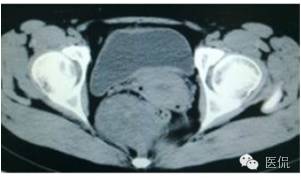

增强动脉期(CT值31HU)